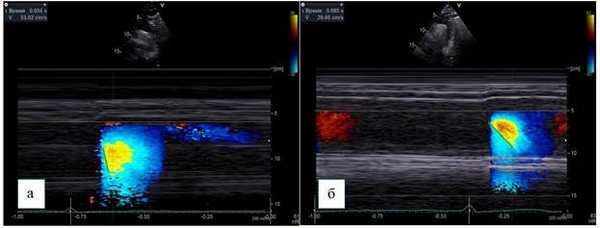

Курсор М-режима располагается параллельно потоку нисходящего отдела грудной аорты, и в сочетании с цветовым доплеровским картированием производится запись цветовой волны потока, получаемой с помощью элайзинг-эффекта, который достигается путем установки предела Найквиста 30-70 см/c.

Скорость распространения потока в цветовом М-режиме определяется как отношение расстояния между точками, отображающими начало и конец наклона цветовой волны потока, ко времени между двумя этими точками (рис. 3).

Рис. 3. Супрастернальная позиция, М-ЦДК нисходящего отдела грудной аорты.

Способ определения СРП:

а - пациент без коронарного атеросклероза, СРП - 530 мм/с,

б - пациент с коронарным атеросклерозом, СРП - 296 мм/c